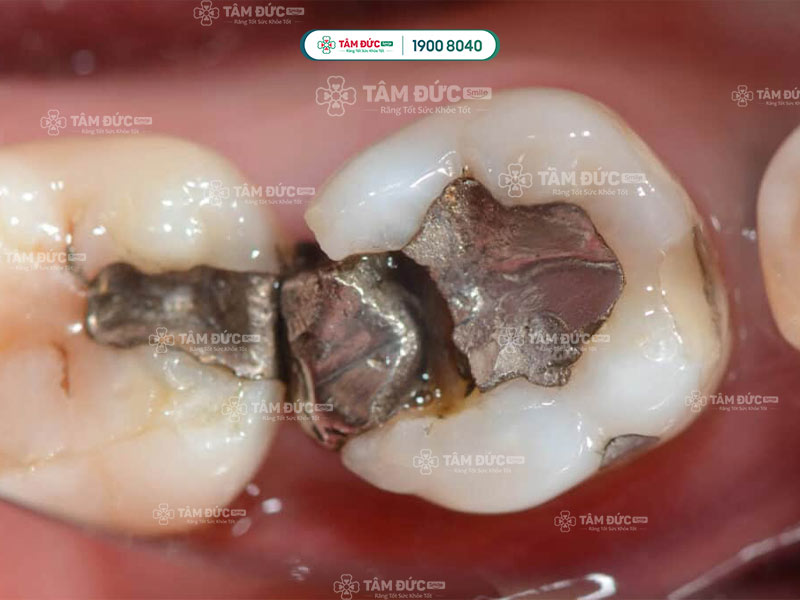

Miếng trám bị vỡ tróc làm thức ăn nhét vào trong gây đau

Kỹ thuật trám răng yếu kém là nguyên nhân phổ biến làm cho răng trám bị đau khi nhai. Khi kỹ thuật trám không đảm bảo, miếng trám không khít với răng, tạo điều kiện cho thức ăn và vi khuẩn dễ dàng xâm nhập vào bên trong răng. Ngoài ra, miếng trám quá cao hoặc quá dày cũng có thể tác động lên răng, dẫn đến đau nhức.

Vật liệu trám răng kém chất lượng có thể gây dị ứng hoặc kích ứng răng, dẫn đến đau nhức. Ngoài ra, vật liệu trám không tương thích với răng cũng có thể khiến miếng trám bị vỡ, bong tróc, tạo điều kiện cho vi khuẩn xâm nhập, gây viêm nhiễm.